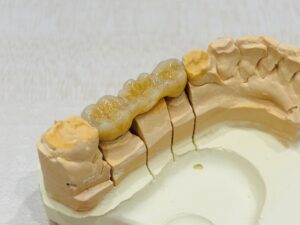

ゴールド

金を主成分とした合金。

抜群の適合性:素材が非常に柔らかいため、歯とつめものの間に隙間ができにくい。

耐久性:錆びにくく、変色もしにくい。

審美性:金属のため存在感はある。特に下顎前歯に近い場所は見えやすい。

二次むし歯:結晶が細かく表面が滑らかなため、プラークがつきにくい。